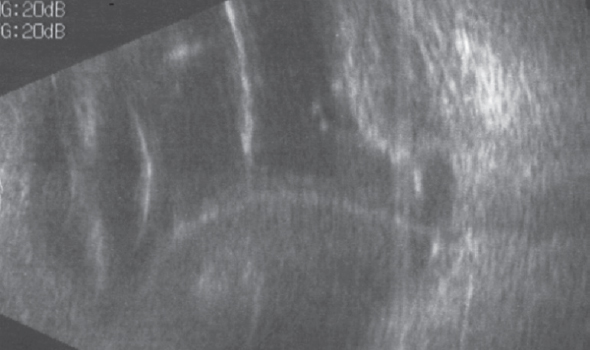

- Ciliochoroidal detachment (Fig. 8) in the early postoperative period in three eyes (4.5%), which was stopped using conservative therapy with corticosteroids; one case required posterior scleral trepanation.

Fig. 8. Echogram of a patient with postoperative total ciliochoroidal detachment / Рис. 8. Эхограмма пациента с послеоперационной тотальной цилиохориоидальной отслойкой